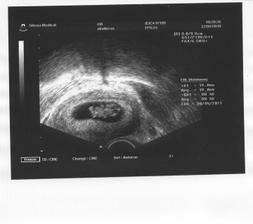

22.9. 9+1tt druhá kontrola. Kobliha roste jako z vody, už má 1,9cm 🙂 vše ok